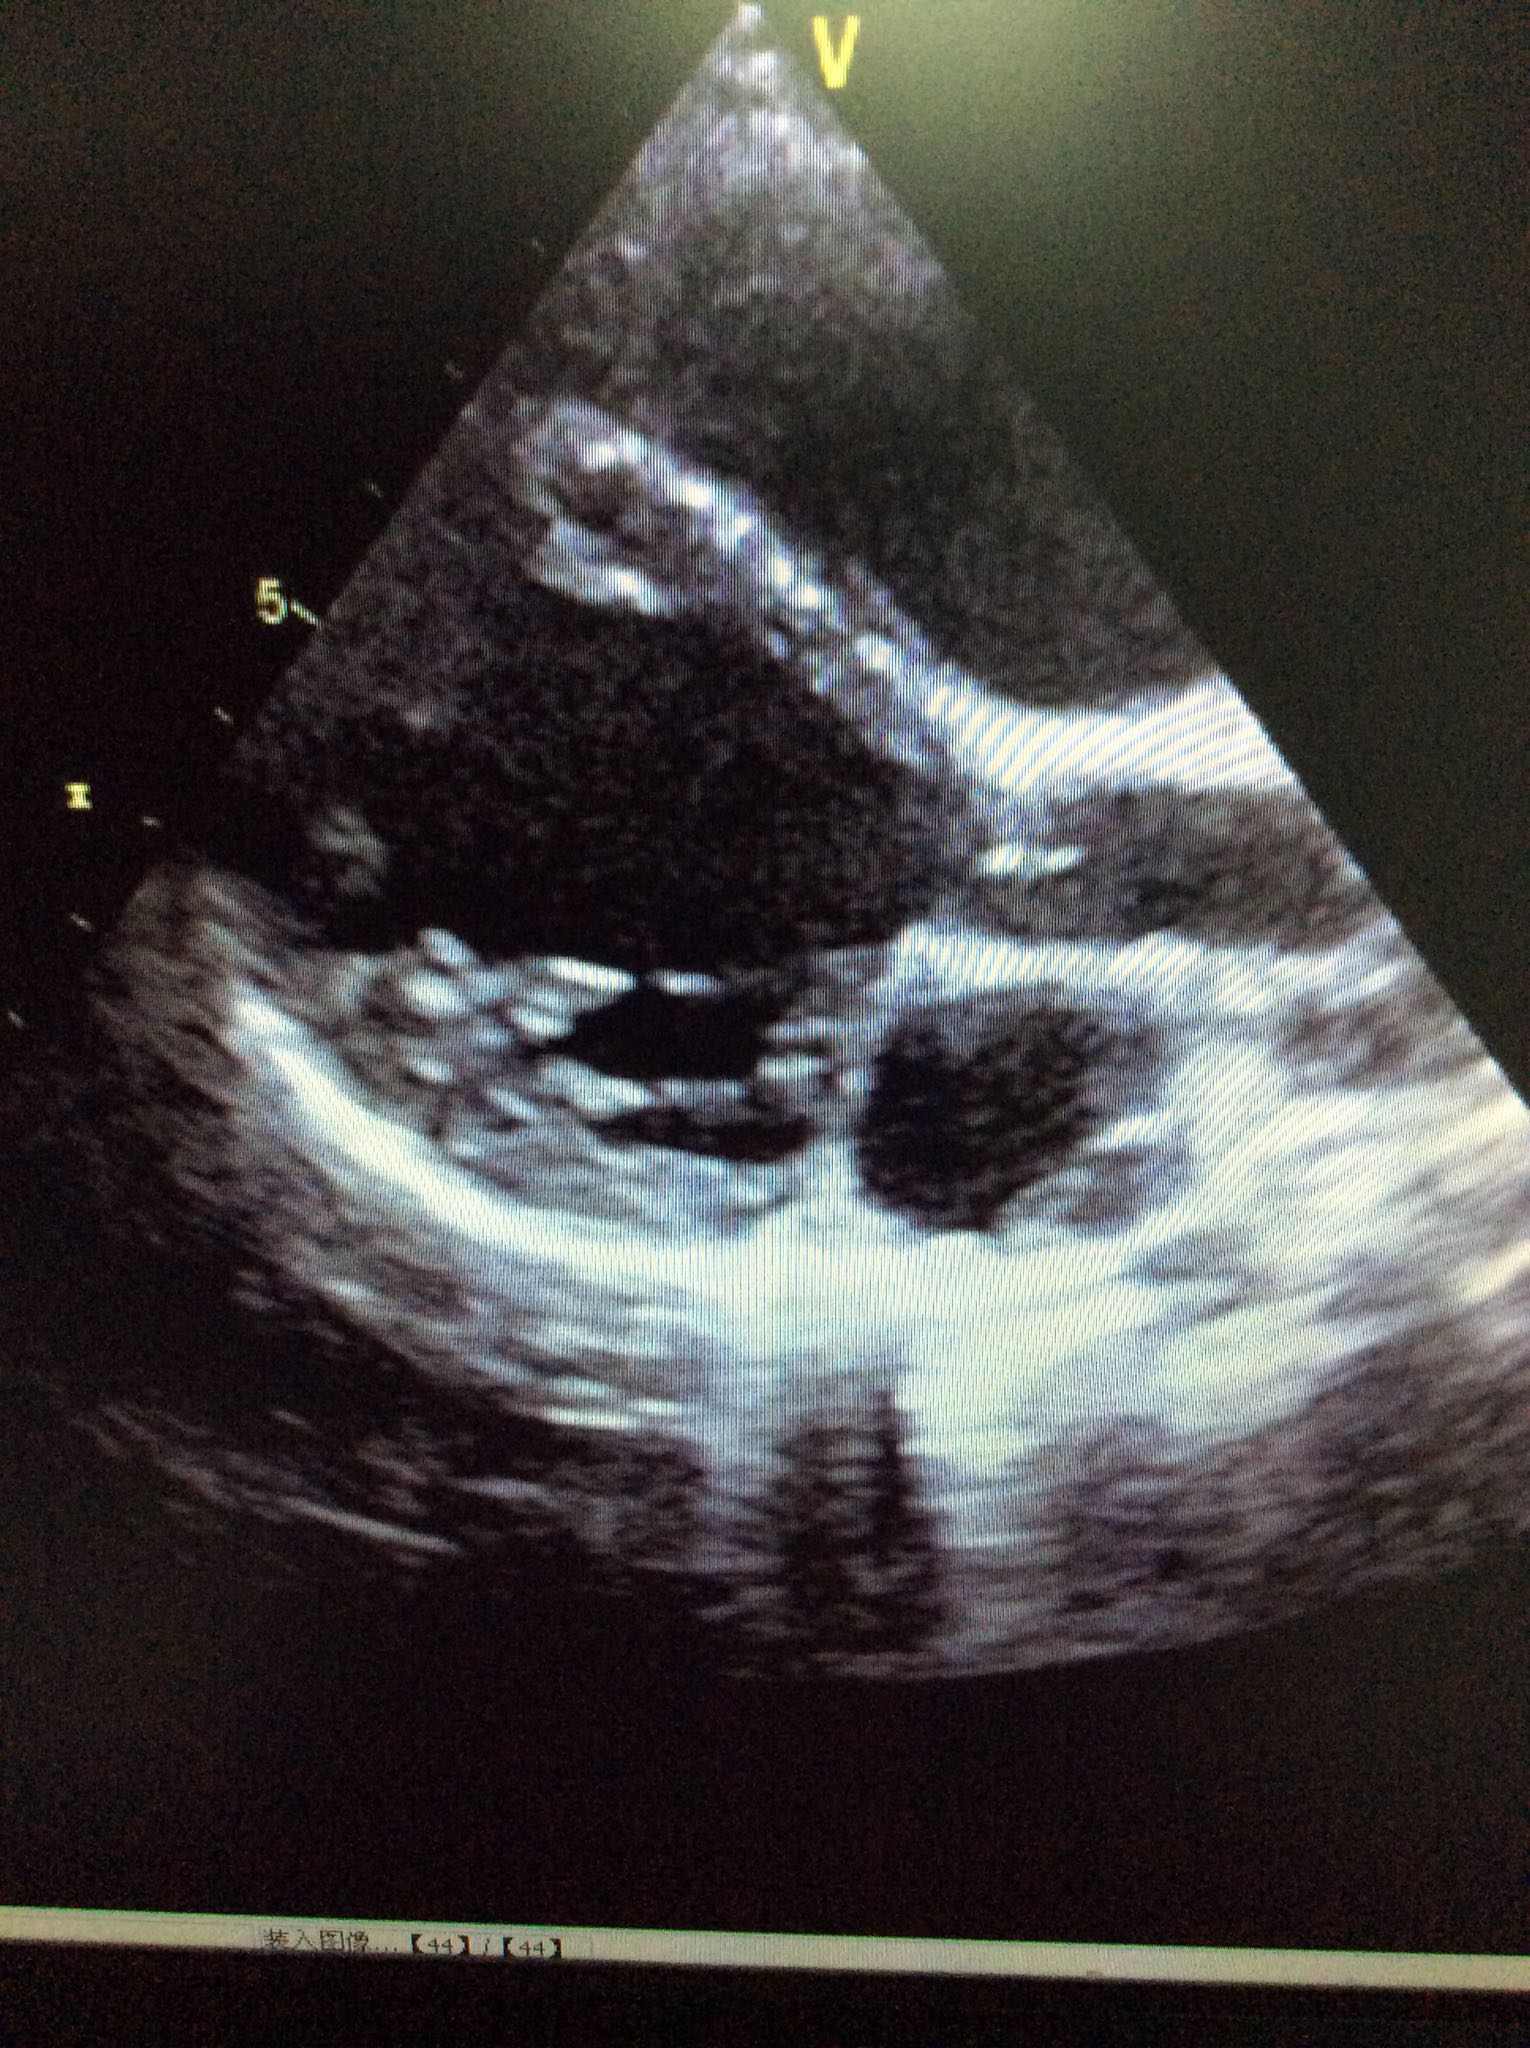

查体:心界增大,心音尚有力,肝脏肋下4cm,脾脏未触及。 心脏超声:全心长大,心机致密化不全,EF40%。心电图:窦性心律,异常Q波。

诊断:心肌致密化不全 进一步完善CTA未见冠脉起源异常,心脏MRI尚未回示。予地高辛强心,卡托普利改善心是重构,利尿,保心等治疗。患儿一般情况可,目前仍在治疗中。